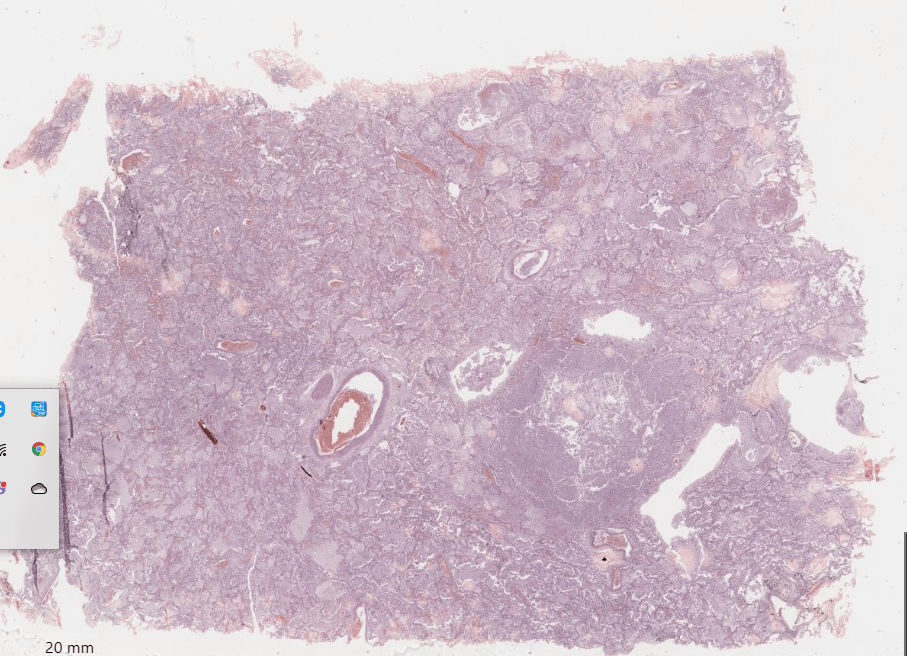

Виждам бял дроб(алвеоли, бронхиоли и кониофаги). В алвеолите и бронхиолите имаме възпалителен инфилтрат ( ексудат ), представен от неутрофилни левкоцити и макрофаги. Участък с разрушаване на междуалвеоларните прегради и изпълване с неутрофилни левкоцити и детрит( излющен епител ). Този участък е добре ограничен абсцес, за разлика от флегмона, който има дифузна инфилтрация от неутрофилни левкоцити.

Абсцес – ограничено гнойно възпаление.

Флегмон – дифузно гнойно възпаление.

Остри и хронични. При острите нямаме пиогенна мембрана, а при хроничните абсцеси имаме пиогенна мембрана( тя е представена от левкоцити, макрофаги, гранулационна тъкан и съединителна тъкан ).